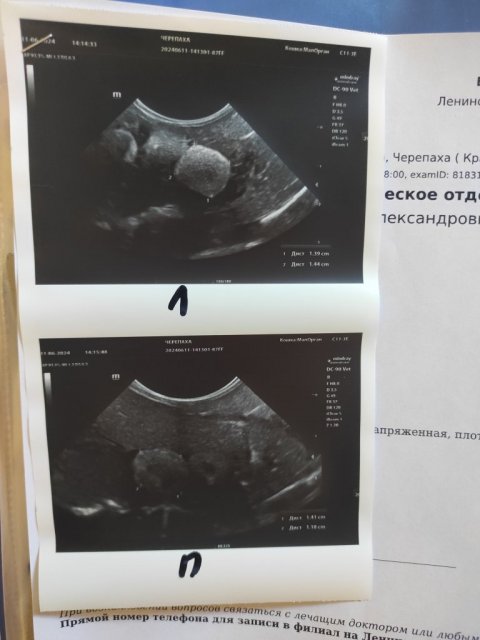

На рентгене изменений нет, на УЗИ куча фолликулов разного размера из которых готовятся выйти яйца.

Врач сказала придти через 2.5-3 недели на контрольное УЗИ посмотреть как развиваются фолликулы и выходят ли яйца.

IMG_20240611_075125.jpg

Заключение врача

IMG_20240611_075141.jpg